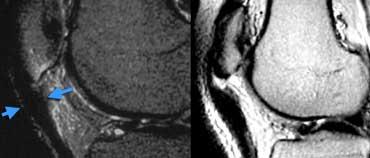

TRÁI: Các bó sợi ACL có hướng bình thường nhưng không bám vào lồi cầu đùi. PHẢI: Dấu hiệu hõm rỗng: dịch áp sát mặt trong lồi cầu ngoài.

Đôi khi dễ đánh giá hơn liệu các bó sợi có còn bám vào xương hay không khi quan sát trên mặt phẳng vành.

Tuyệt đối không được có dịch áp sát mặt trong lồi cầu ngoài.

Nếu có dịch ở vị trí này, được gọi là ‘dấu hiệu hõm rỗng’, cho thấy ACL đã bị bong khỏi điểm bám trên lồi cầu đùi.

Trên mặt phẳng ngang có dấu hiệu hõm rỗng (mũi tên vàng) ở vị trí lẽ ra ACL phải bám vào lồi cầu. Ở mức thấp hơn (sang phải), ACL đứt đã dính sẹo vào PCL (mũi tên xanh lá).

Trên mặt phẳng ngang cũng phải thấy dây chằng nằm sát bên lồi cầu.

Ở mức thấp hơn, chúng ta thấy ACL đứt bám dính vào dây chằng chéo sau.

Chúng đã dính vào nhau thành sẹo.

Đây là hình ảnh rất thường gặp trong đứt ACL mạn tính.

Sự dính sẹo này tạo ra góc gấp cấp tính của dây chằng.

Mặc dù ACL đã dính vào PCL, nhưng vẫn không đủ vững và cần phải tái tạo.